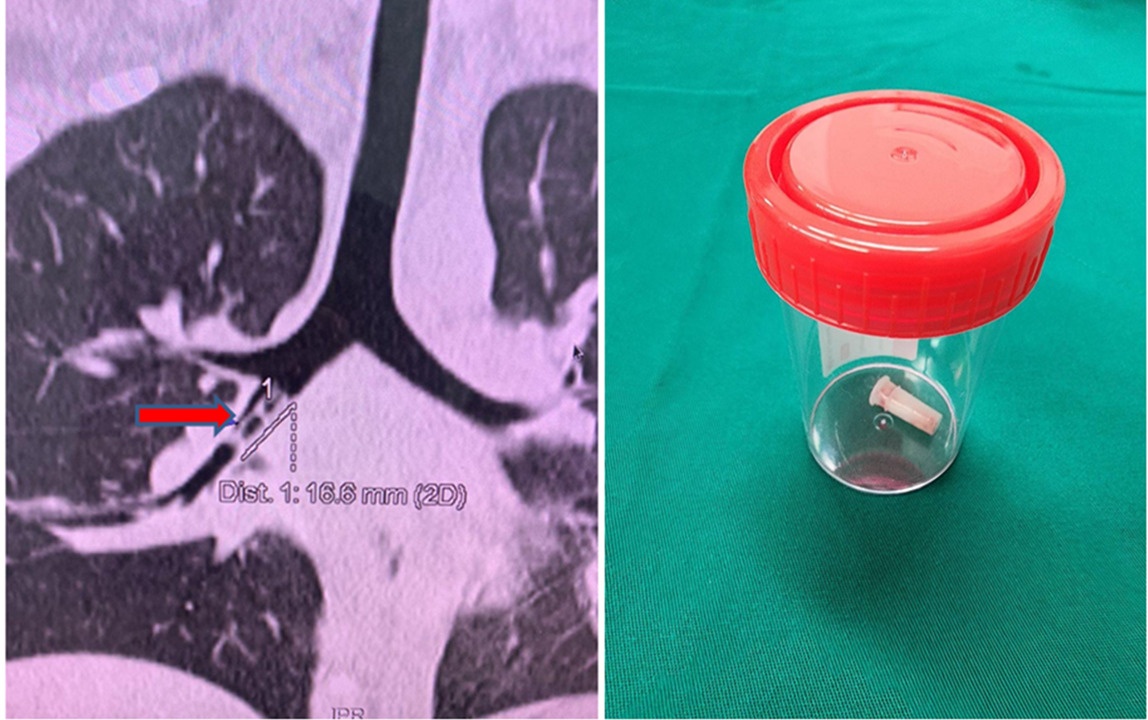

Dị vật là chiếc kèn đồ chơi được gắp ra từ phế quản của bé trai. Ảnh: BSCC.

Tuy nhiên, kết quả X-quang cổ và ngực thẳng chưa ghi nhận dị vật cản quang. Bác sĩ tiếp tục chụp CT Scan lồng ngực, may mắn phát hiện dị vật dạng ống rỗng nằm trong phế quản trung gian bên phải.

Ống nội soi thăm dò đến tới phế quản trung gian, bác sĩ phát hiện dị vật màu trắng đục, rỗng, bít gần hoàn toàn phế quản trung gian. Dị vật được gắp ra là ống nhựa kèn kích thước 0,5x2 cm.